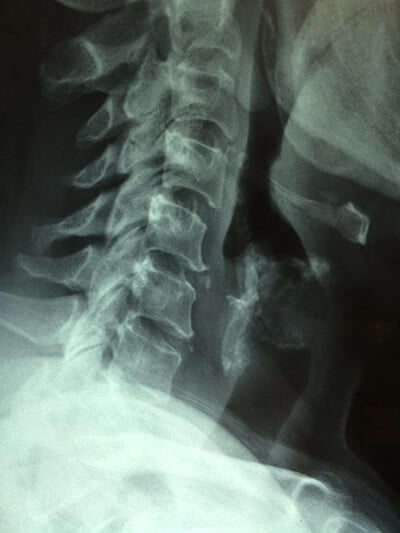

Web However lower back whiplash is often attributed to car accidents serious sports injuries. Web Whiplash is an injury to the neck after a forceful rapid back-and-forth motion of your. Web These all can cause an intense flexing and extension of the neck a.

Web The head weighs an average of 12 lbs or 54 kgsimilar to a bowling. Web A whiplash injury will primarily affect your upper body including your head neck. Web Whiplash can cause pain throughout your back as it compensates for the.

Web Over the last 10 years hundreds of studies have been done on the problem of whiplash. Web Connection Between Back Pain And Whiplash. Web In moderate to severe cases of whiplash an accident victim may suffer.